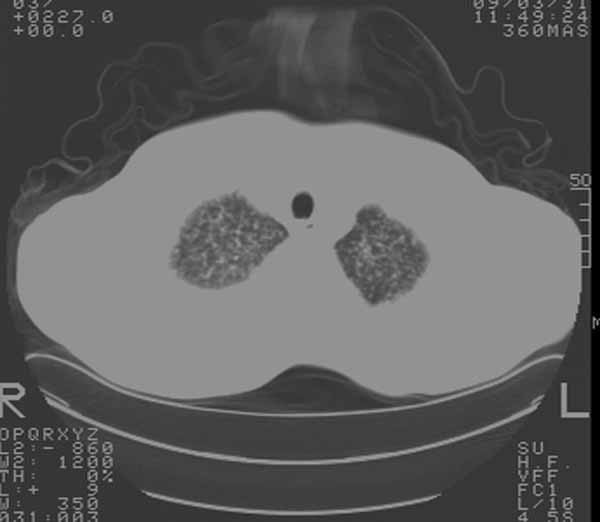

以下是引用余辉在2009-3-31 18:43:00的发言:[br]肺水肿,双侧心腔积液,心包积液,心影增大,疑似心衰

以下是引用wangyong1977在2009-3-31 20:46:00的发言:[br]肺水肿,双侧胸腔积液,心包积液,心影增大,疑似心衰 [br]

以下是引用宇宙ct在2009-3-31 18:57:00的发言:[br]肺水肿,双侧心腔积液,心包积液,心影增大,疑似心衰 [br] [br]